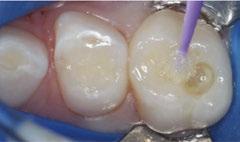

The 5-year-old patient featured in this case study did not benefit from early oral care and had multiple carious lesions. Considering the young age, high caries risk, and the uncertainty of compliance with follow-up appointments, I wanted to restore and seal all teeth in one visit. One quadrant is shown in this case study. The carious lesion on tooth J (65) was cavitated and prepared, restored, and sealed. Tooth I (64) was non-carious and would only be sealed (Figure 1).

surface of tooth I (64) was also lightly abraded with a diamond bur (Figure 2). The preparations were selectively etched with phosphoric acid, rinsed, and lightly dried (Figure 3). Bonding agent was applied to the entire occlusal surfaces of both teeth, air thinned, and light-cured (Figure 4).

Tooth J (65) was bulk-filled with Activa Kids. For this fast injection technique, I place the dispensing tip at the floor of the preparation and extrude the material without removing the tip until the preparation is completely filled (Figure 5). I like to do some minor manipulation of the filling material with hand instruments to create anatomy, as well as to ensure the material is flush with the surface of the preparation, and no air is trapped inside. Activa Kids is dual-cure, ideal for bulk filling, and can be cured with all lights. A thin topcoat of Activa Presto was placed as a sealant on the entire occlusal surface of teeth I and J (64 and 65) (Figure 6). Figure 7 shows the final clinical situation.

Figure 1 (left): Caries lesion on tooth J (65). Figure 2 (center): Preparation of tooth J (65) and abraded occlusal surface of tooth I (64). Figure 3 (right): Selective etch of enamel Figure 4 (left): Bonding agent is applied to both teeth I and J (64 and 65). Figure 5 (right): The preparation is filled with ACTIVA Kids Figure 6 (left): A thin topcoat of ACTIVA Presto is applied to the occlusal surfaces of teeth I and J (64, 65). Figure 7 (right): Final result